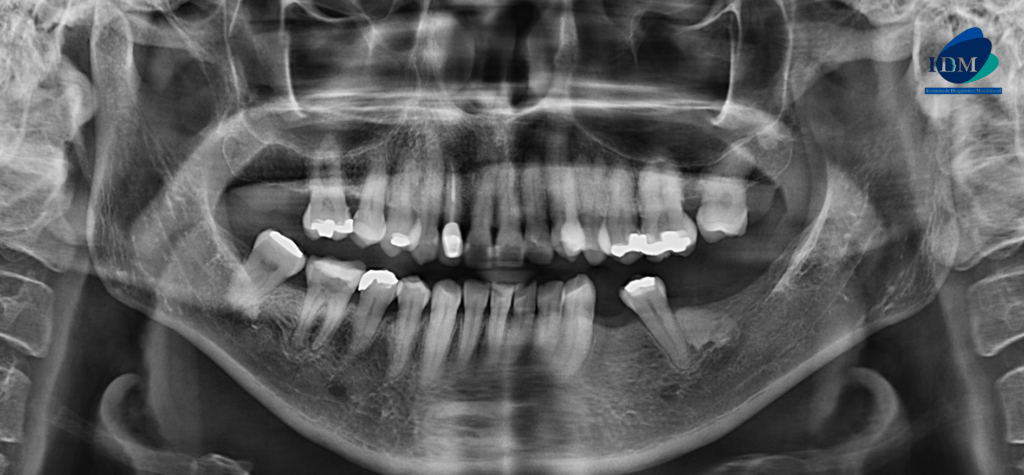

Radiografia Panorámica

A la evaluación de la radiografía panorámica se observa a aplanamiento del contorno condilar bilateral, neumatización de ambos senos maxilares, reabsorción ósea moderada del proceso alveolar, la presencia de una imagen radiopaca de límites definidos y forma irregular en cuerpo mandibular del lado izquierdo compatible con una osteoesclerosis idiopática, múltiples restauraciones coronarias y la pieza 12 que presenta corona protésica, espigo intrarradicular y obturación de conducto.